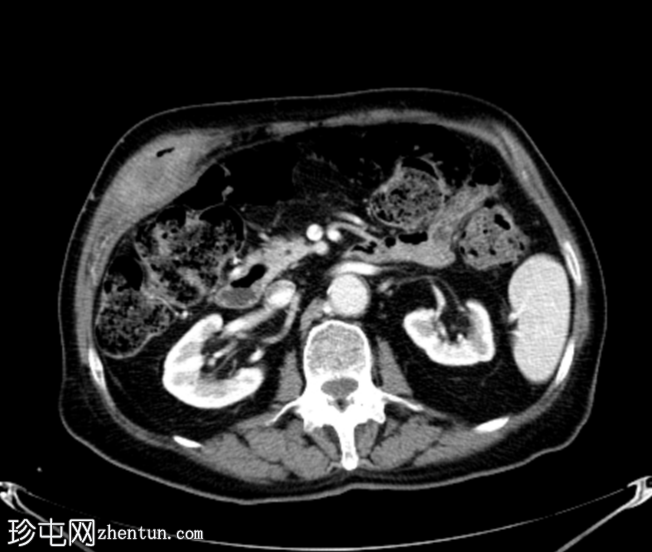

4.png

轴位增强扫描

门静脉期

胆囊底部可见一枚较大的(3厘米)高密度结石,胆囊壁增厚并强化,主要位于胆囊底部。胆囊壁可见一小穿孔,感染扩散至胆囊外,并在肝下区可见气体腔。感染进一步扩散至腹壁肌肉,腹壁肌肉内可见脓肿,边缘强化明显,囊性坏死中心,腔内可见气体腔。十二指肠第一段与炎症胆囊粘连。

检查结果提示急性胆囊炎合并腹壁脓肿。

患者接受了紧急手术,术中发现急性胆囊炎,并发胆囊壁穿孔、胆囊十二指肠瘘和前腹壁脓肿形成。